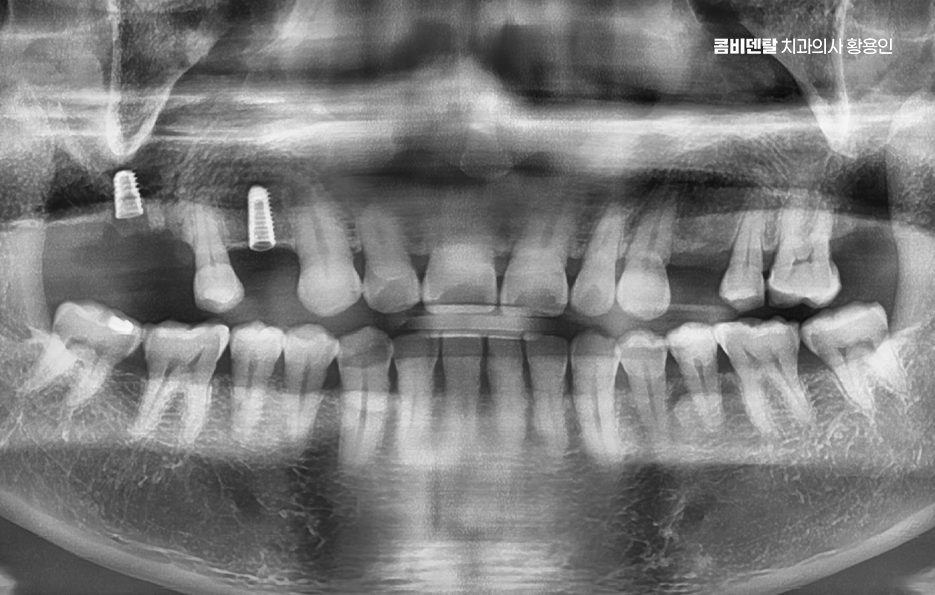

그래서 이런 문제들을 막기 위해서라도 임플란트는 어금니 상실 후 중요한 치료 옵션으로서 임플란트는 빠진 치아의 뿌리 역할까지 해주기 때문에, 단순히 공간을 채우는 게 아니라 턱뼈에 자극을 줘서 뼈 흡수를 막아주고, 위아래 치아가 정상적으로 맞물릴 수 있게 해주며 다른 보철 방식과 비교해도 장기적인 안정성과 기능 회복 면에서 유리한 거예요.

임플란트를 빨리 하는 게 좋은 이유는, 시간이 지나면서 턱뼈가 점점 흡수돼버리면 임플란트를 심을 뼈 자체가 부족해지는 상황이 생기기 때문이며 이때는 뼈이식이나 상악동 거상술 같은 추가 수술이 필요하게 되고, 치료 기간도 길어지고, 비용도 많이 올라가기 때문에 어금니가 빠졌다고 방치하는 시간만큼 치료는 더 복잡해질 수 있다는 점에서 어금니 없으면 얼굴 발음 및 오늘 알아본 것처럼 다양한 문제로 이어질 수 있음을 잘 이해하여 빠르고 나에게 맞는 치료 계획을 세우시고 장기적으로는 수명 유지까지 잘 고려하여 치료 계획을 잘 세워보시길 바라고 있어요